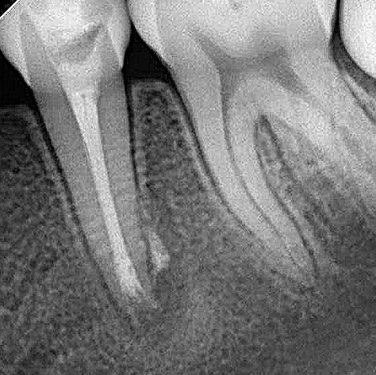

The patient did not report any painful symptoms during the months of treatment. In the follow-up session, six months after root canal filling, the tooth did not show sensitivity to the percussion tests. Radiographically, there was regression of the periapical lesion and tissue formation in the apical region of the tooth (Figure 5).

Figure 5B. Radiographic aspect after six months of follow-up.